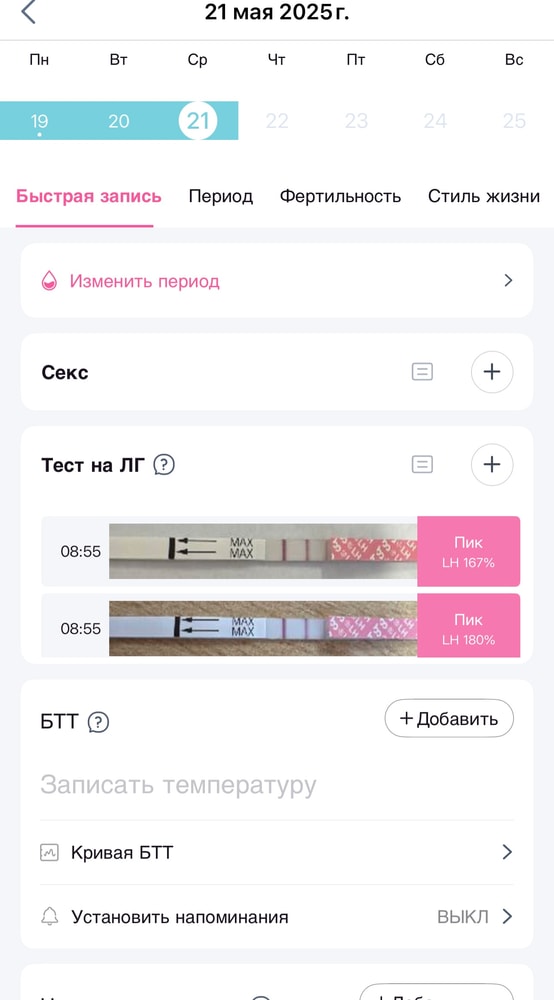

Вчера утро:

Сегодня день:

Что-то я понять не могу, свой организм вместе с тестами на овуляцию.

понедельник вечер:

Вторник 7 утра:

Тестик на овуляцию ярчает) я радуюсь как ребенок😂 овуляция с СПКЯ, большая редкость. Последняя была в январе (стимулированная), а предпоследняя в мае 2024 года. 20 д.ц и счаст